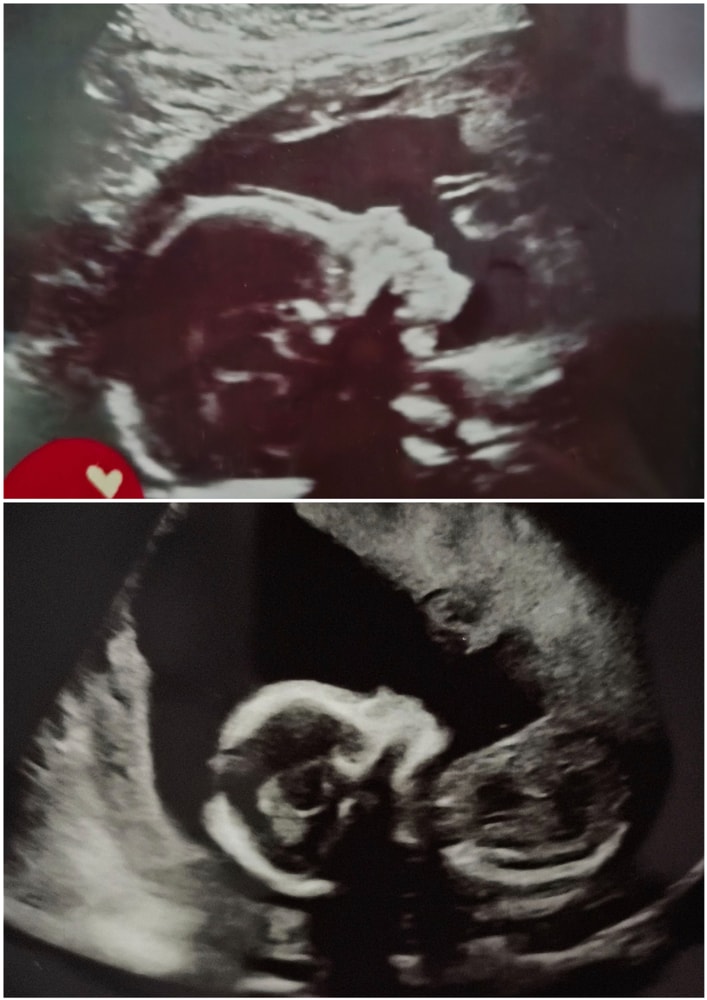

УЗИ, КТГ, доплерНаправили меня в ркб в Казань, для прохождения аллерголога и эндокринолога. И там же появилась возможность пройти 2 скрининг. Фото моей 1 дочки на 2 скрининге, ей сейчас 7 лет) и моей второй ♥️в животике

Ждём тебя ,солнышко 🤗